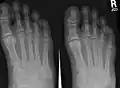

الرسم إلى اليمين نظرة من أعلى القدم، والرسم إلى اليسار نظرة من أسفل القدم :

A- عظم العقب (Calcaneus).

B- عظم الكاحل (Talus bone).

C- العظم النردي (Cuboid bone).

D- العظم الزورقي (Navicular bone).

E- عظم إسفيني وحشي (Lateral cuneiform bone).

F- عظم إسفيني أوسط (Intermediate cuneiform bone).

G- عظم إسفيني إنسي (Medial cuneiform bone). * العظام المبيّنة باللون الرمادي الداكن (الغامق) هى عظام مشط القدم (Metatarsal bones). * العظام المبيّنة باللون الرمادي الفاتح هى سُّلاَمَيات القدم (Phalanges of the foot).